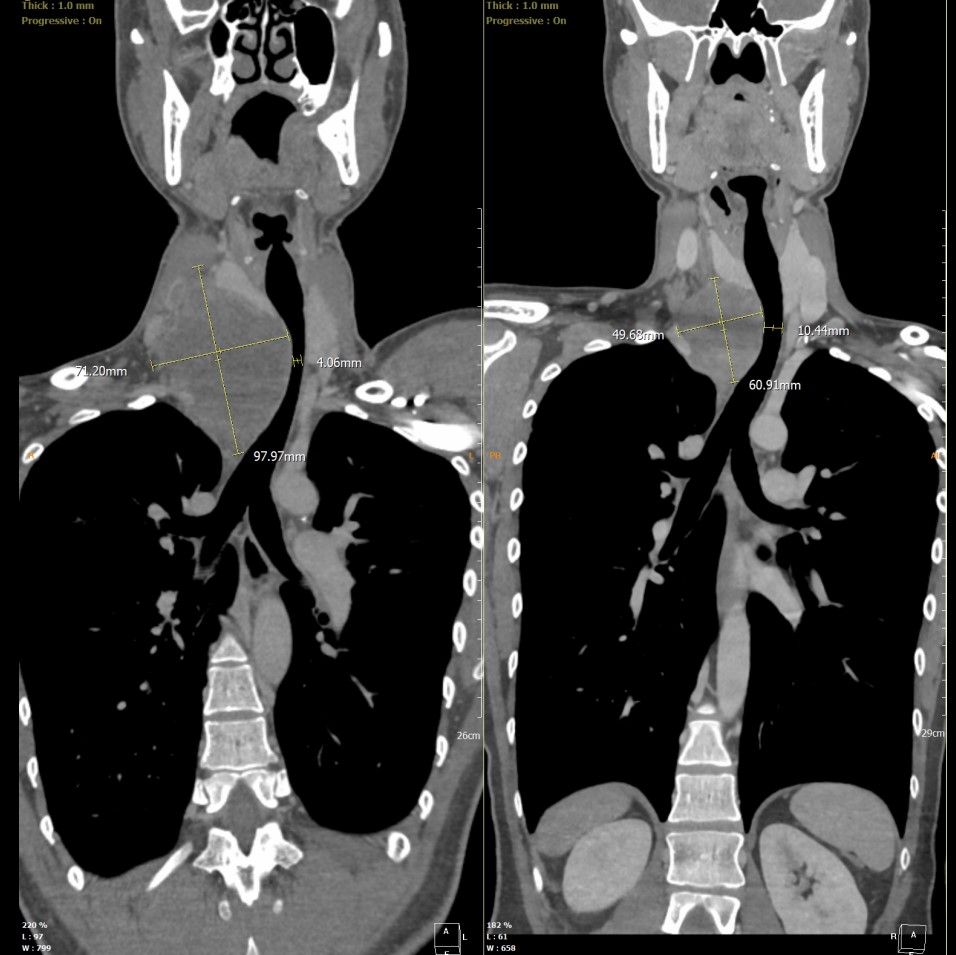

CT scan of Neng's tumour showing the size and how it is pressing against his airway.

“Advanced imaging showed that the tumour has encased and compressed the carotid artery, which is the main blood supply to the brain. The cancerous tumour in the right neck also displaced and compressed the airway. The tumour had extended down into the chest, reaching the level of the arch of the aorta close to the heart,” said Dr Eng Chee Yean, Consultant ENT, Head and Neck, Thyroid and Parathyroid Surgeon (lead surgeon).

This posed significant risks due to the proximity of the tumour to major nerves, blood vessels, airway, and the heart. A failed surgery could mean coma, stroke, dependence on breathing machine permanently, or even death. Neng's case was further complicated by the rapid growth of the tumour compressing his airway causing difficulty in breathing and therefore required urgent surgery. The patient and surgical team were battling against time.